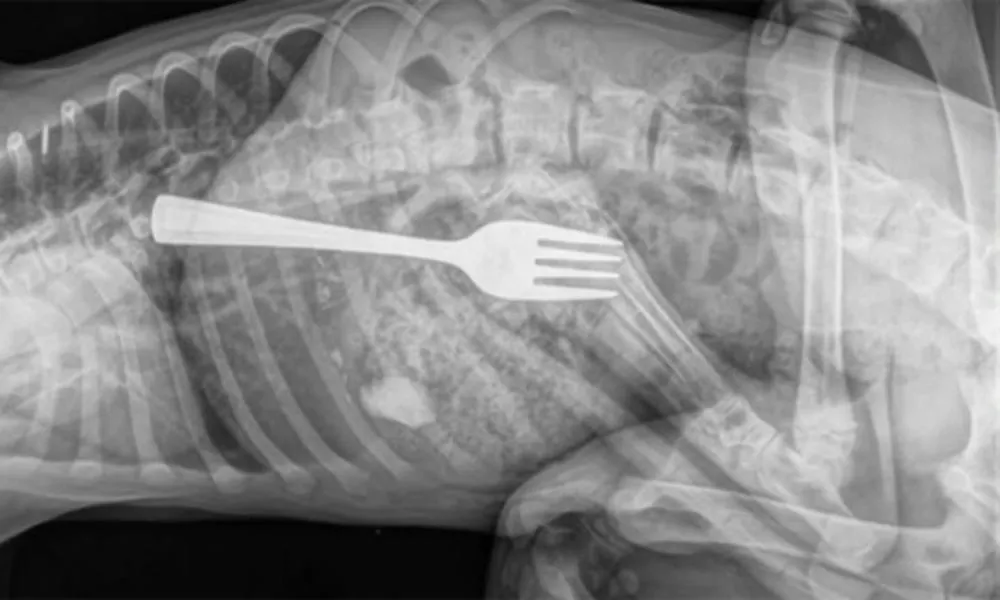

Mulher engole garfo durante refeição em Guanambi

Um caso inusitado e de risco à saúde foi registrado em Guanambi, no sudoeste da Bahia, na última sexta-feira (26). Uma mulher, que não teve a identidade divulgada, precisou de atendimento de urgência após engolir um garfo enquanto se alimentava.

A paciente foi encaminhada inicialmente ao Hospital Geral de Guanambi, onde exames de imagem identificaram o objeto preso no esôfago, em posição considerada de alto risco. Diante da gravidade, os médicos determinaram a transferência imediata para Vitória da Conquista, onde uma equipe especializada realizou o procedimento de remoção.

O rápido encaminhamento foi decisivo para evitar complicações mais graves. O estado de saúde da paciente após a intervenção não foi informado.